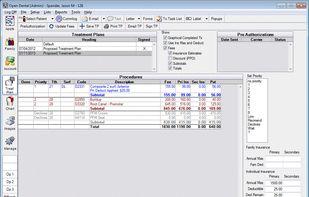

Clear.Dental is described as 'Open Source Dental Practice and Treatment Planning Software' and is an app. There are four alternatives to Clear.Dental for a variety of platforms, including Windows, Web-based, Android, iPhone and iPad apps. The best Clear.Dental alternative is Open Dental, which is both free and Open Source. Other great apps like Clear.Dental are Dentrix, Dentem and 365Apex.